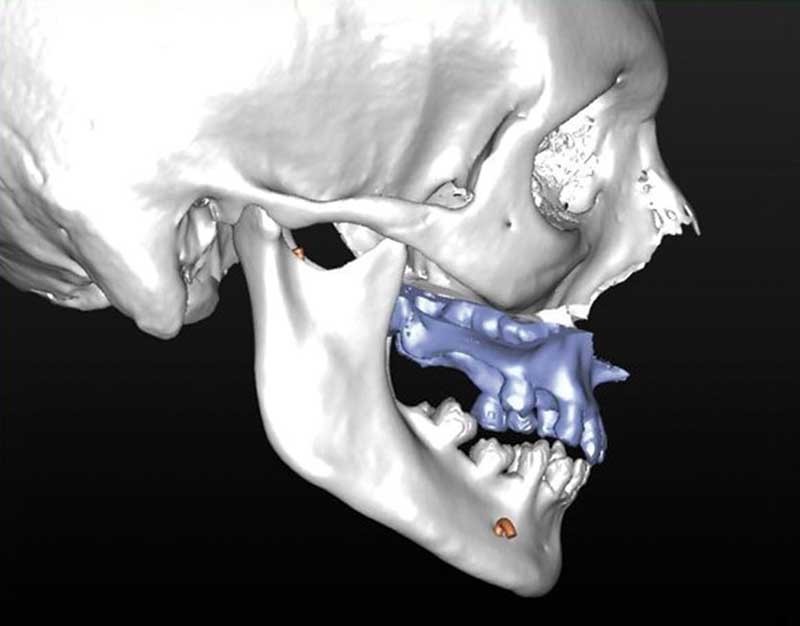

L’enregistrement des classiques modèles en plâtre (en occlusion corrigée de Classe 1) à l’aide d’un scanner conventionnel (format DICOM) ou par empreinte optique (format STL) est ensuite intégré au squelette dento-squelettique ; étape désignée « matching des modèles ».